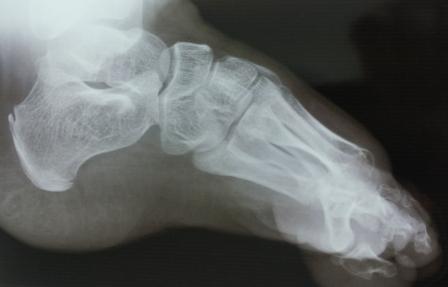

Уважаемые коллеги, специалисты подиатрии! Сегодня обратилась девочка

2004 г.р. , лет 7-8 назад оперирована в одной центральной клинике,

по-видимому, по поводу косолапости, ахиллопластика и аппаратом

Илизарова( документов нет).

Просит исправить деформацию и чтобы могла одеть нормальную обувь .Фото и

Р-графия предлагается, где имеется вывих в плюснефаланговом суставе и

медиальная девиация всех пальцев, 1- палец пассивно поднимается до

горизонтали, при этом подошвенная фасция сильно натягивается, но

разгибания нет, медиальная девиация пальцев исправлению поддается без труда.